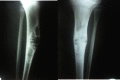

Case report: A 13 year old girl presented with pain and swelling of the (R) leg since 2 months following a trivial injury at school. Examination revealed a 5×3cm tender swelling on the anteromedial aspect of the middle third tibia. Radiographs and MRI, revealed an eccentric expansile lytic lesion, which was multilocular and was present at the junction of the metaphysis and diaphysis on the antero -medial aspect of tibia. The cortex had ballooned out and there was a possibility of an impending fracture. Biopsy was done which revealed osteofibrous dysplasia. We did an extraperiosteal excision of the lesion. To fill the cavity we harvested 10 cm of the contralateral fibula and since there was still space in the cavity, we packed bone graft substitute (hydroxyapatite crystals) into the defect. The surgical management of osteofibrous dysplasia is controversial. Various methods of treatment of such cases have been described in literature. The use of synthetic graft is an option in these patients as it reduces morbidity; and in our case we had good graft incorporation with this method.